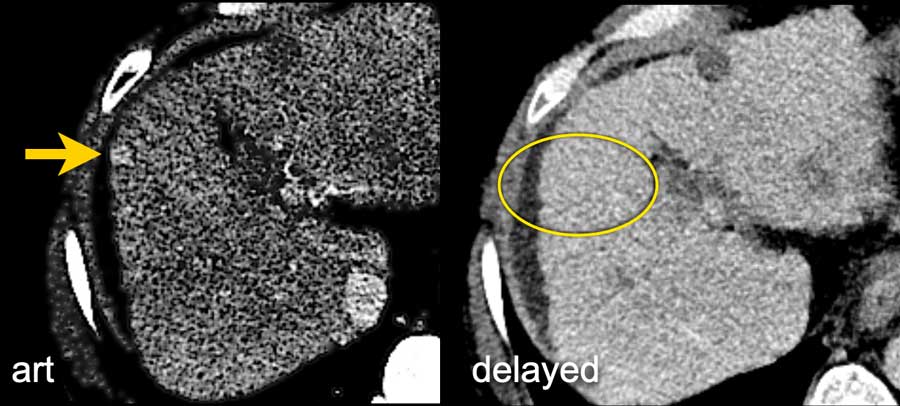

Li Rads M Lesion

The series is edited and supervised by our associated editor dr. The Radiology Assistant Li Rads

The Radiology Assistant Li Rads from radiologyassistant.nl

Li Rads M Lesion. The series is edited and supervised by our associated editor dr. pmc free article google scholar A perthes lesion is a labroligamentous avulsion like a bankart, but with a medially stripped intact periosteum. The classification system is meant to be used in livers that have risk factors for hcc (e.g. Results major features (arterial phase hyperenhancement, washout, capsule, and threshold growth) had a sensitivity of 88.5%, 60.6%, 32.9%, and 41.6%, and a specificity of 18.